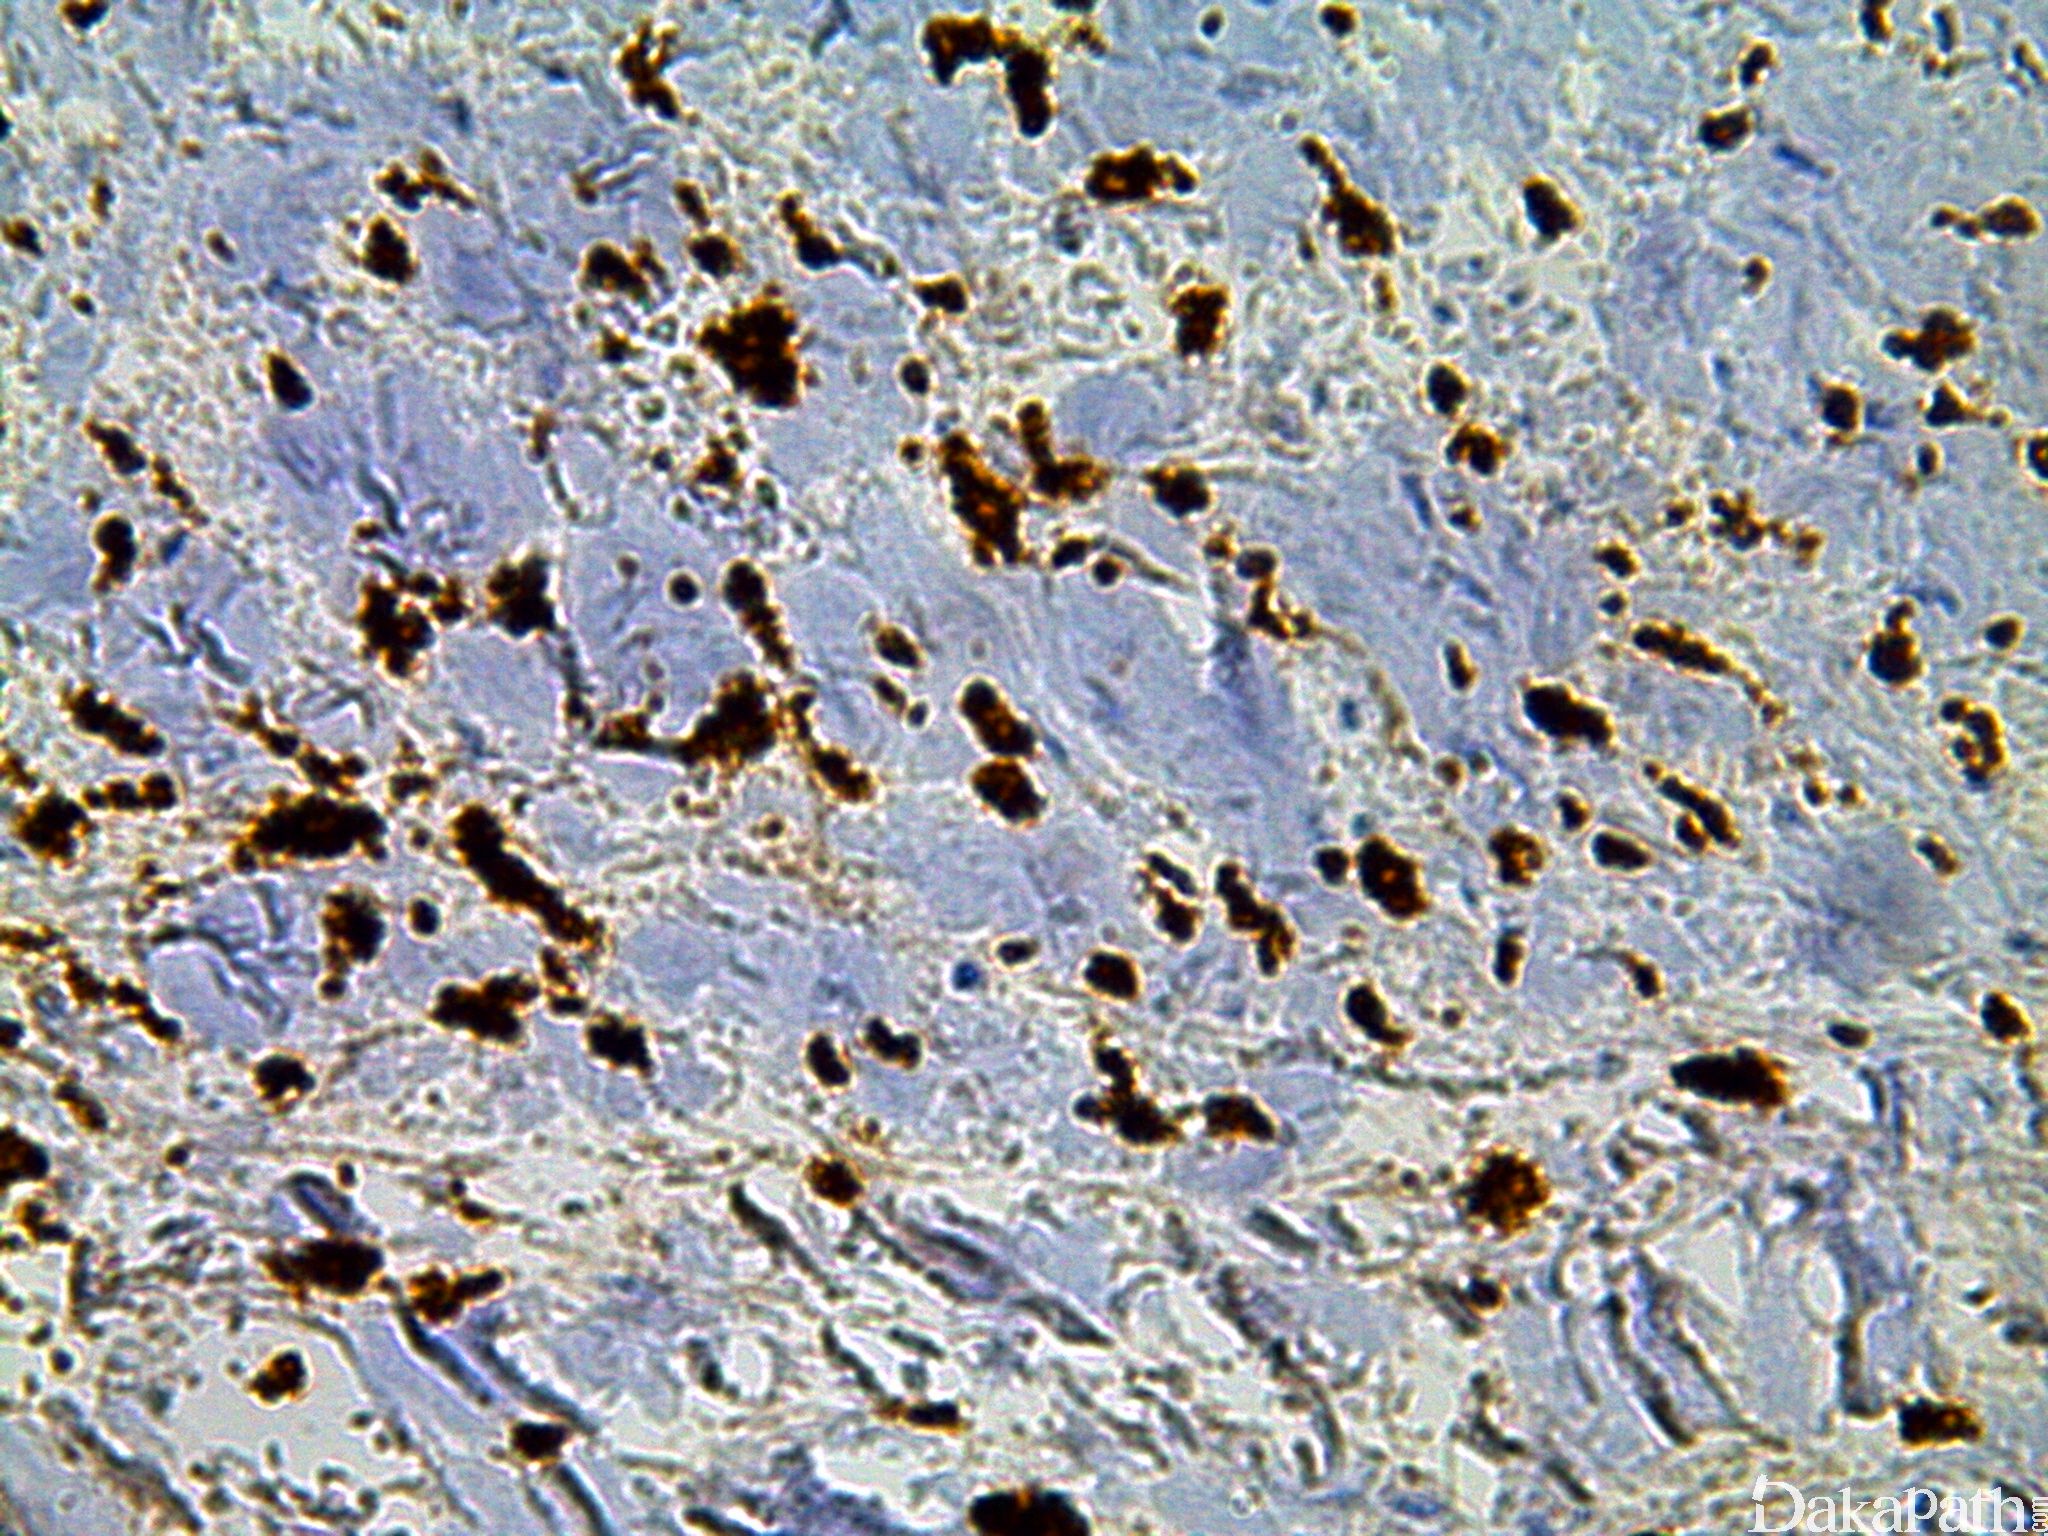

CD163

是一种 I 型膜蛋白,介导细胞吞噬结合珠蛋白与血红蛋白复合体,几乎表达于所有组织的单核巨噬细胞。不表达于不成熟的单核细胞、肺泡内的巨噬细胞及小胶质细胞;不表达于淋巴滤泡生发中心、套区的 FDC 细胞。

信号定位: 胞膜